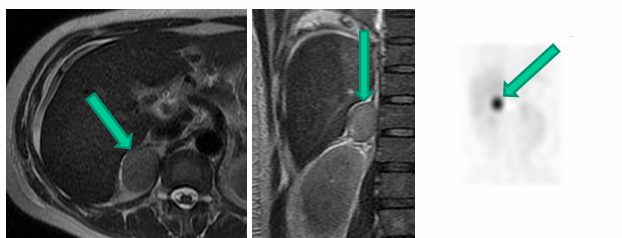

-pheochromocytoma

germline mutations associated with pheochromocytoma and paraganglioma